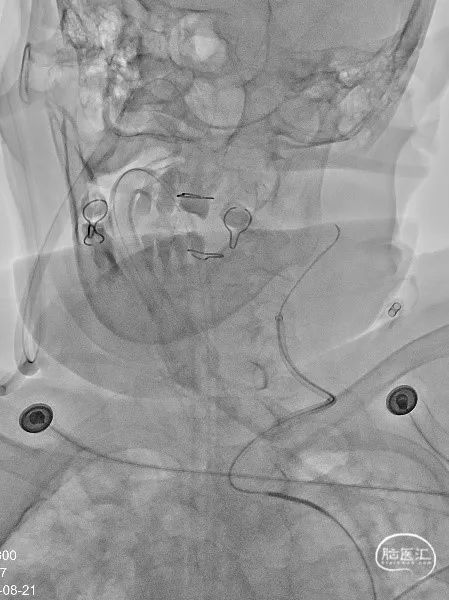

Neuron Max 长鞘先通过颈总动脉迂曲,然后6F 115CM Tethys®中间导引导管“裸奔”到达海绵窦段,推送过程顺畅。

弹簧圈先推出两个环,然后半释放支架覆盖A1起始部动脉瘤瘤颈,填塞Jasper®SS 1.5x3弹簧圈,过程流畅,微导管非常稳定,然后再填塞一枚Jasper®SS 1.5x2弹簧圈,瘤腔致密栓塞。

最后更换工作角度,微导管重新塑形后超选进入后交通动脉瘤腔内,全部释放支架,5枚Jasper®电解脱弹簧圈致密栓塞后交通动脉瘤。